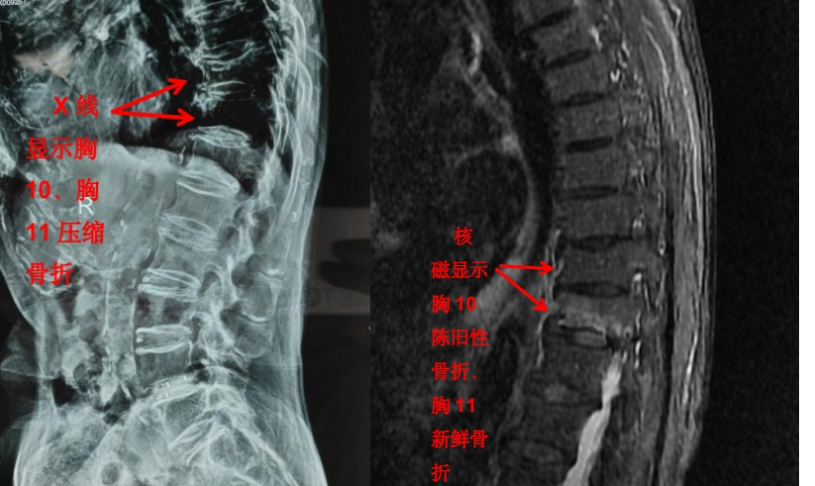

但是對(duì)于大部分軟組織病變?nèi)缱甸g盤(pán)、椎管內(nèi)神經(jīng)、有沒(méi)有占位性病變等卻無(wú)能為力。如果患者有壓縮骨折,X 光片也無(wú)法判斷是新鮮骨折還是陳舊骨折,這樣也就無(wú)法定制下一步診療計(jì)劃。

隨著科技進(jìn)步及醫(yī)學(xué)的發(fā)展,核磁已經(jīng)是脊柱外科不可或缺的檢查手段。對(duì)脊柱、韌帶、椎間盤(pán)、椎管內(nèi)神經(jīng)及椎旁組織顯影都優(yōu)于 CT,通過(guò)腰椎核磁我們可以直觀地看到椎間盤(pán)突出的程度、神經(jīng)受壓的程度,以及壓縮骨折的新鮮程度。

核磁相對(duì)于 CT 和 X 線檢查顯像更清晰,內(nèi)容更全面,那么所有腰背部疼痛的患者來(lái)就診后都應(yīng)該做核磁嗎?答案當(dāng)然是否定的。X 光、CT 和核磁這三種檢查側(cè)重點(diǎn)不同,在對(duì)疾病的診治過(guò)程中都有著不可替代的作用。

核磁雖然顯像更全面,但都是層掃,直觀整體的信息欠缺,X 光片雖然內(nèi)容少,但可以顯示出脊柱整體的影像。幾種檢查互相補(bǔ)充,可以讓疾病診斷更加明確。

前面提到的腰椎壓縮骨折,X 光片可以看出楔形變,但無(wú)法判斷新鮮骨折還是陳舊骨折,進(jìn)一步完善腰椎 MRI 才能明確診斷,做出下一步治療計(jì)劃。